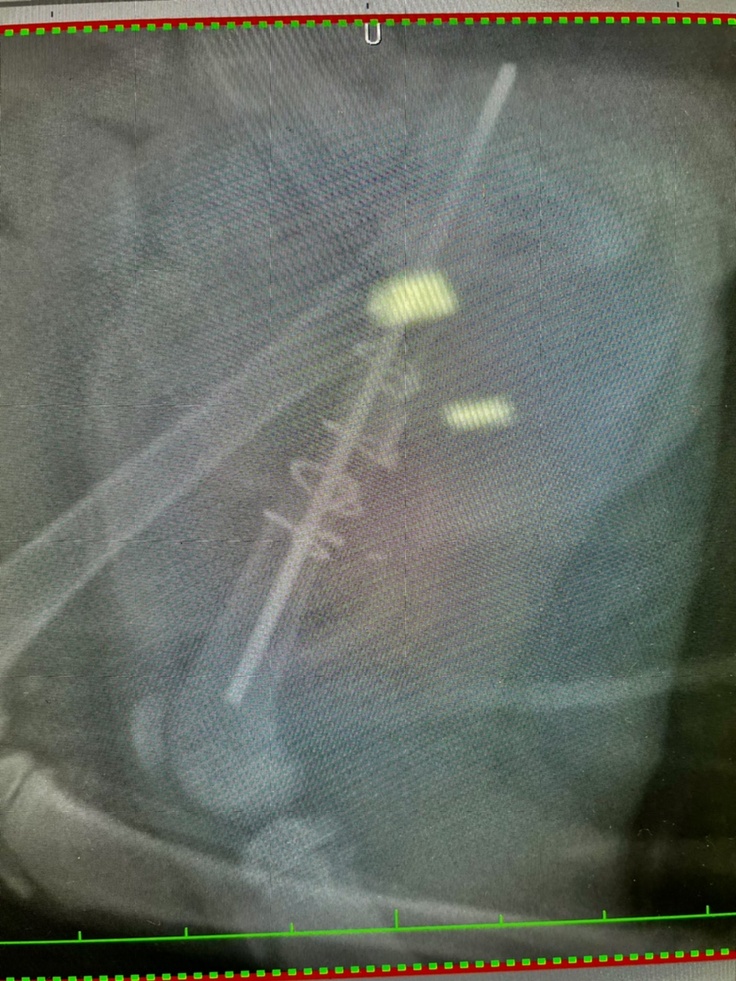

②手術&退院(8月20日〜8月21日)

8月20日に無事に手術が終わり、8月21日に退院しました。ステンレスのピンとワイヤーで骨を固定しています。服薬は難しいとのことで2週間効果が続く抗生剤の注射を退院時に接種しています。

③手術後の初めての受診(8月31日)

本来であれば8/28受診予定でしたが、動物病院が急遽8/24〜8/30まで臨時休診となりました。8/31より診療再開したので受診し、抜糸を行い、レントゲンを撮りました。

縫合後の皮膚の治りは順調です。骨も少しずつですが、くっついてきています。しかし固定したピンがズレてきているため、皮膚を突き抜け、飛び出してくる可能性があるとのことでした。飛び出してきた場合はまた抜き取る処置をしなくてはならないとのことでした。次の受診は9/11を予定しています。

↓[8月31日撮影]